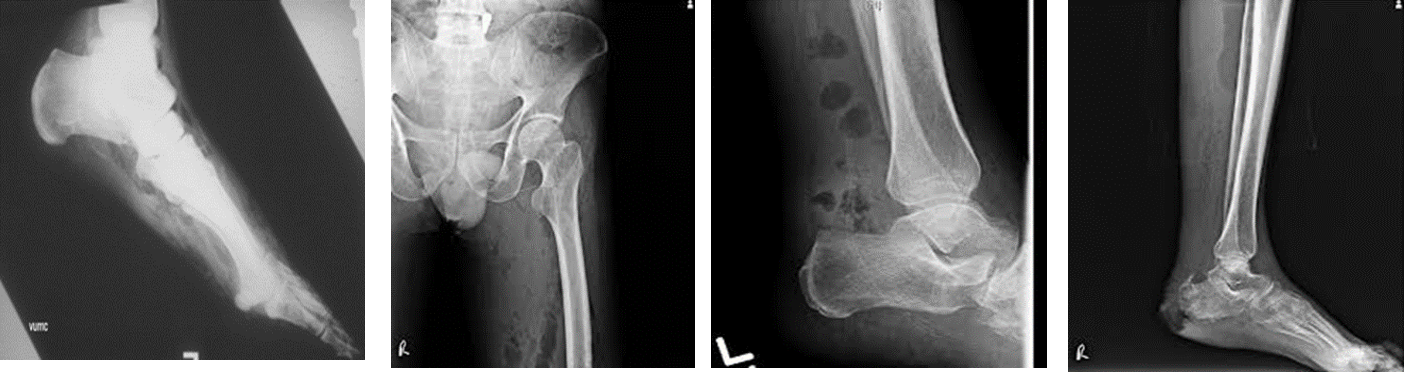

- X-ray: ( appearance of gas under skin and in muscles.)